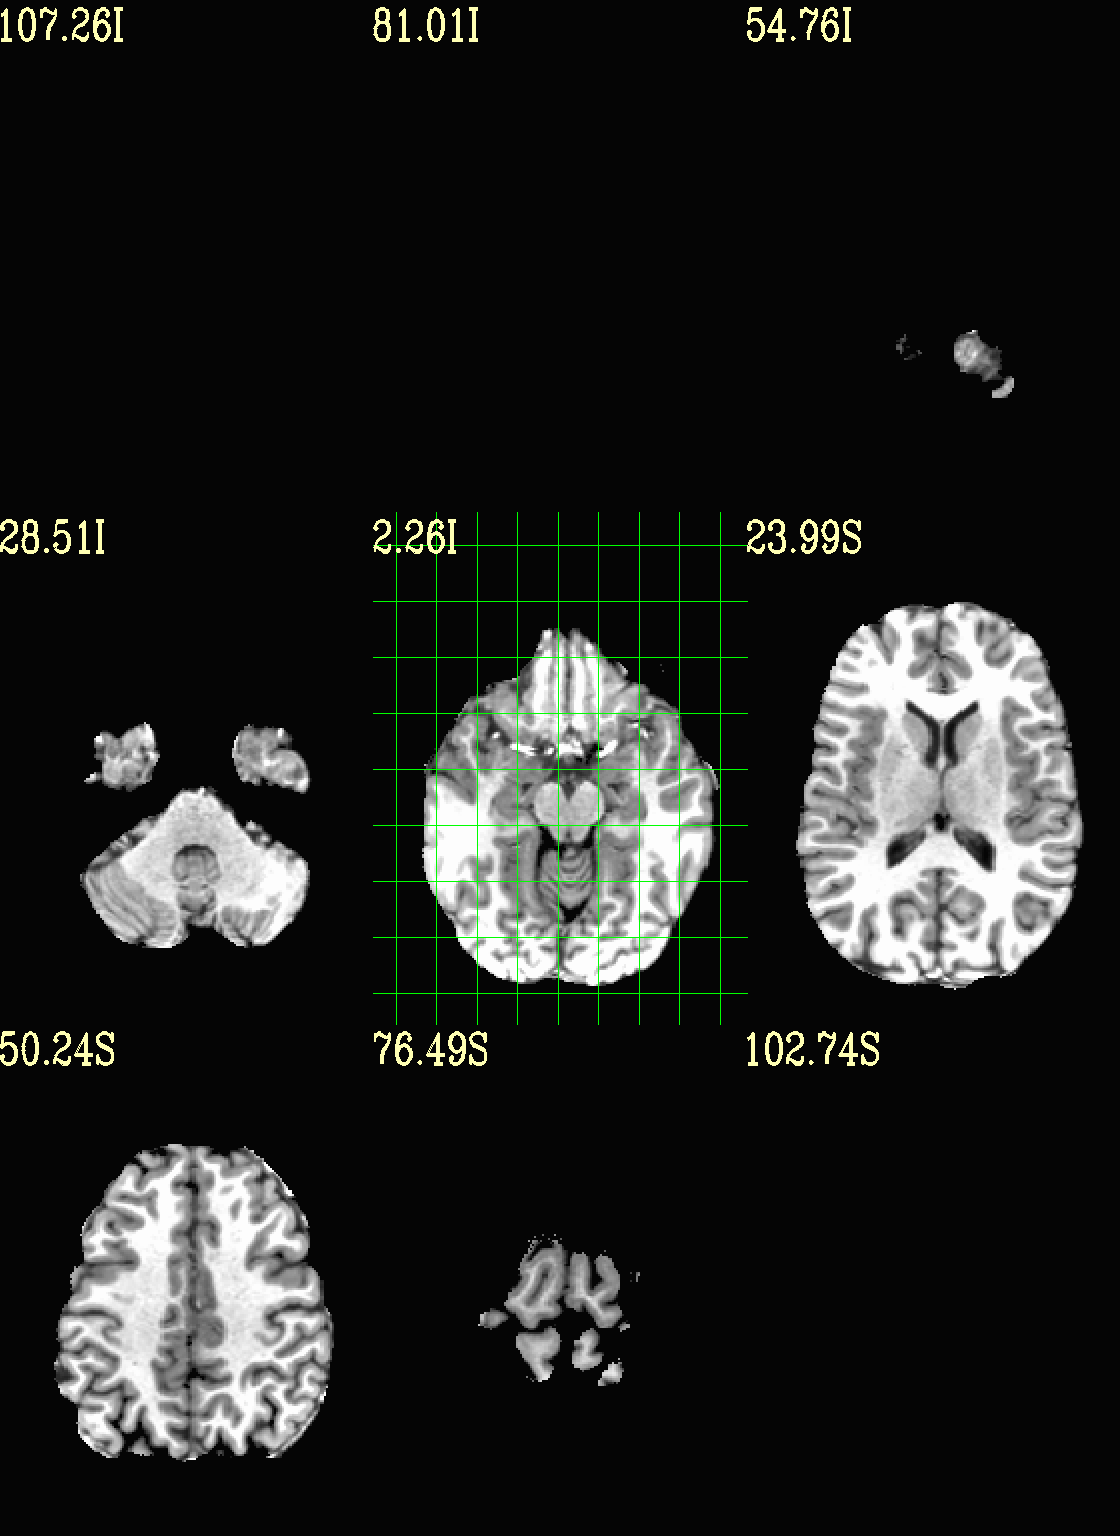

Ex. 0: Simple underlay viewing¶

Simply view the (non-skullstripped) anatomical volume as an underlay by itself. Might be useful to check for artifact, coverage, etc. The full crosshair grid shows where slices are taken from, and might be useful for seeing the relative alignment/axialization of the brain.

Unless specified otherwise, the ulay black/white mapping is to 0%/98% of voxels in the whole volume. The AFNI GUI uses 2%/98% of slicewise percentiles by default, but since default viewing here is montage-based, volumewise is implemented by default for consistency across both the individual view-plane montage as well as across three view-planes that are created per command execution.

set opref = QC/ca000_anat_def

@chauffeur_afni \

-ulay anat+orig.HEAD \

-prefix ${opref} \

-set_xhairs MULTI \

-montx 3 -monty 3 \

-label_mode 1 -label_size 4

Ex. 1: Moving/selecting view slices¶

By default, the image slices are set as follows: if there are N total images in the montage, place N along each axis spaced as evenly as possible (as done in the previous example).

However, users can specify either the (x, y, z) or (i, j, k) location of the central slice, as well as spacing between each of the N slices (the “delta” number of rows/columns between image slices). In this example the central image is placed at the location (x, y, z) = (-10 4 3), and different slice spacing is specified along different axes.

set opref = QC/ca001_anat_mv_slices

-set_dicom_xyz -20 4 3 \

-delta_slices 5 15 10 \